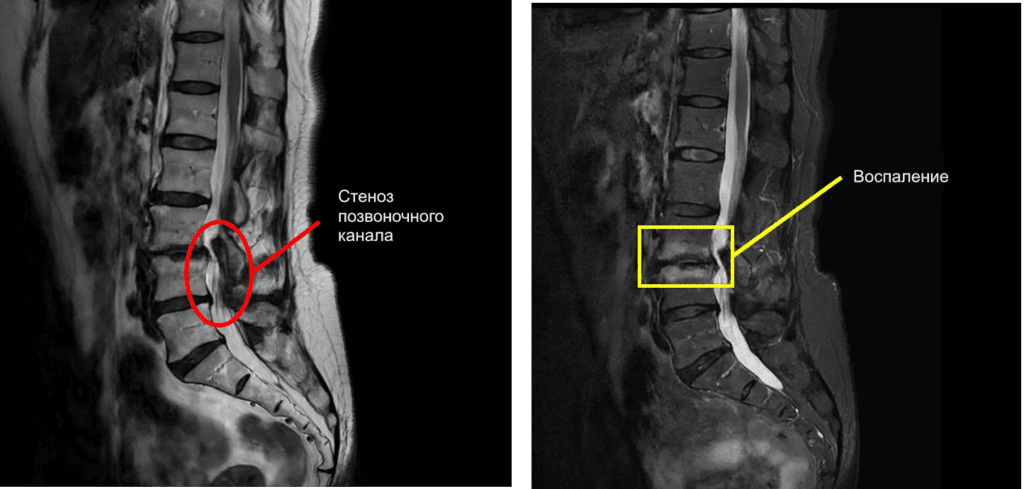

По данным МРТ выявлен стеноз позвоночного канала на уровне дисков L3/L4 и L4/L5, а также воспаление в области диска L3/L4.

Стеноз позвоночного канала на уровне диска L3/L4 является основной причиной болей и онемения.

Поскольку выявлено воспаление в области диска L3/L4, рекомендовано сначала провести лечение воспаления озоном, а после того, как воспаление пройдет, провести селлгель-терапию.